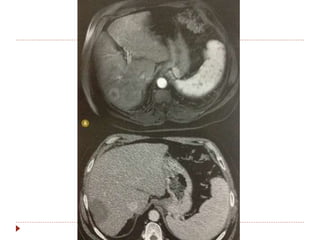

 Hepatocarcinomas

 Se tratados com embolização, radiofrequencia ou crioablação

resposta se não houver realce periférico pelo contraste na TC ou

RM.

Outros critérios modificadoresdo RECIST  Alguns tumores especiais já consideram densidade e padrão de realce.  Mesoteliomas  Medida dificultada pela curvatura da parede torácica.  Medir perpendicular a parede, em 2 locais, cada um em 3 níveis = soma das 6 medidas. Preferir porção superior do tõrax.  GIST  Boa resposta = redução de 10% dimensões e 15% da atenuação na TC.  Progressão = lesões novas, aumento tamanho 20% ou não mudança de densidade.  Hepatocarcinomas  Se tratados com embolização, radiofrequencia ou crioablação resposta se não houver realce periférico pelo contraste na TC ou RM.